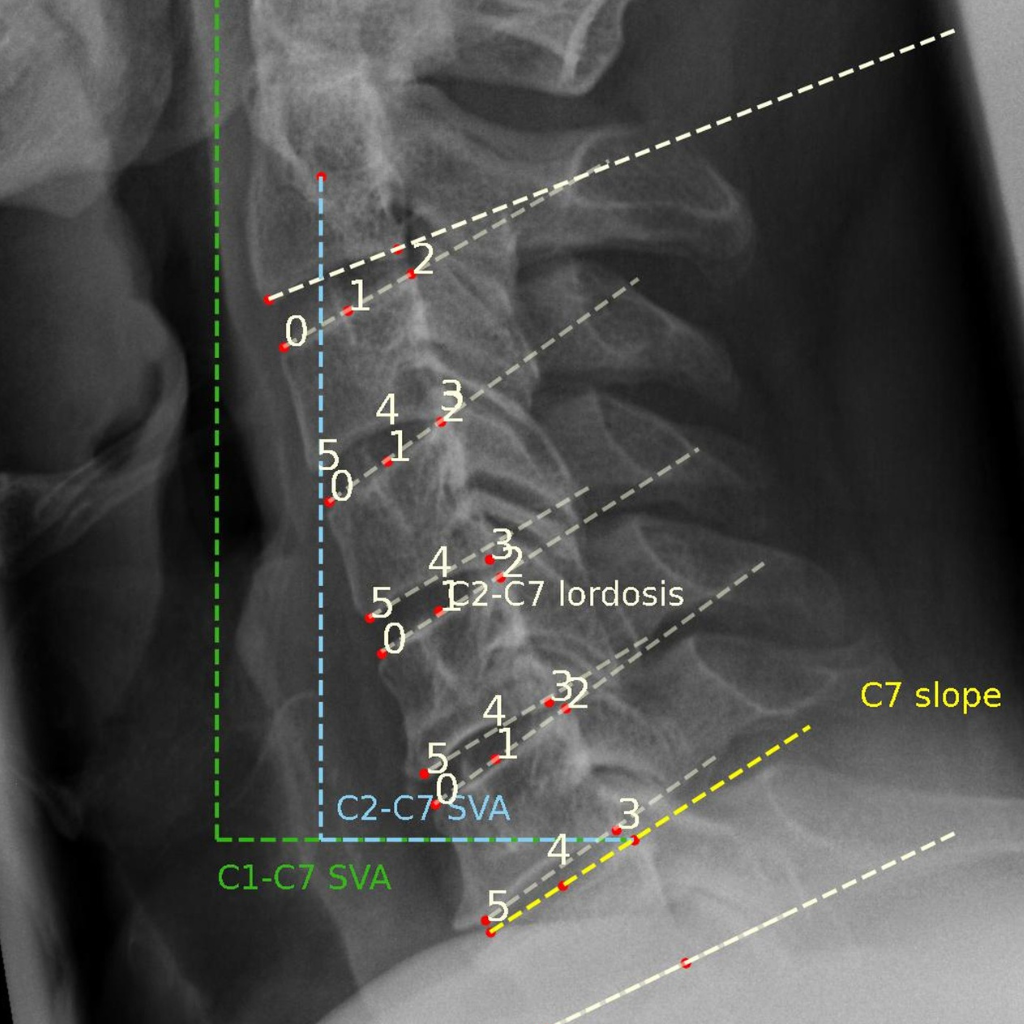

Spine

- Range of Motion (RoM)

- Center of Rotation (CoR)

- Disc height

- Anteroposterior instability

- Cobb Angles

- Cervical & Lumbar Lordosis

- Segmental motion analysis

- Fusion assessment

- Implant subsidence

- And over 100 additional parameters

Spinal image analysis for clinical trials, registries, and research.

We have extensive experience designing and executing clinical studies with imaging endpoints for all major spinal therapies, including fusion, motion preservation, and deformity correction—from early feasibility through post-market surveillance.

The FDA-approved Functional X-Ray Analysis software (FXA) of our imaging core lab is capable of automatically evaluating over 150 radiographic parameters of the spine, hip, or knee. The reproducibility of the measurements is on file with FDA 510(K).

Explore some of our most popular automatically assessable quantitative radiographic parameters below.

Range of Motion (RoM)

The Angular Motion/Range of Motion (RoM) is a quantitative parameter used to evaluate spinal fusion.

It is measured as the angular difference of two adjacent vertebrae during the flexion and the extension posture of a patient and is reported as an absolute value in degrees (°). RAYLYTIC’s FXA software has been shown to measure RoM 15 times more precisely than experienced physicians (Schulze et al., J Biomech 2011).